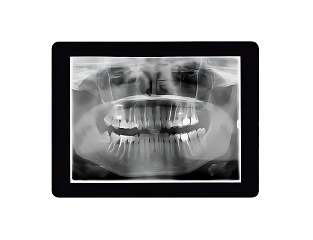

Advanced Care & Comfort

Our state-of-the-art technology ensures precise treatment and faster, more comfortable results.

The iTero scanner captures detailed 3D images of your teeth, enhancing the accuracy of your treatment plan without messy impressions.